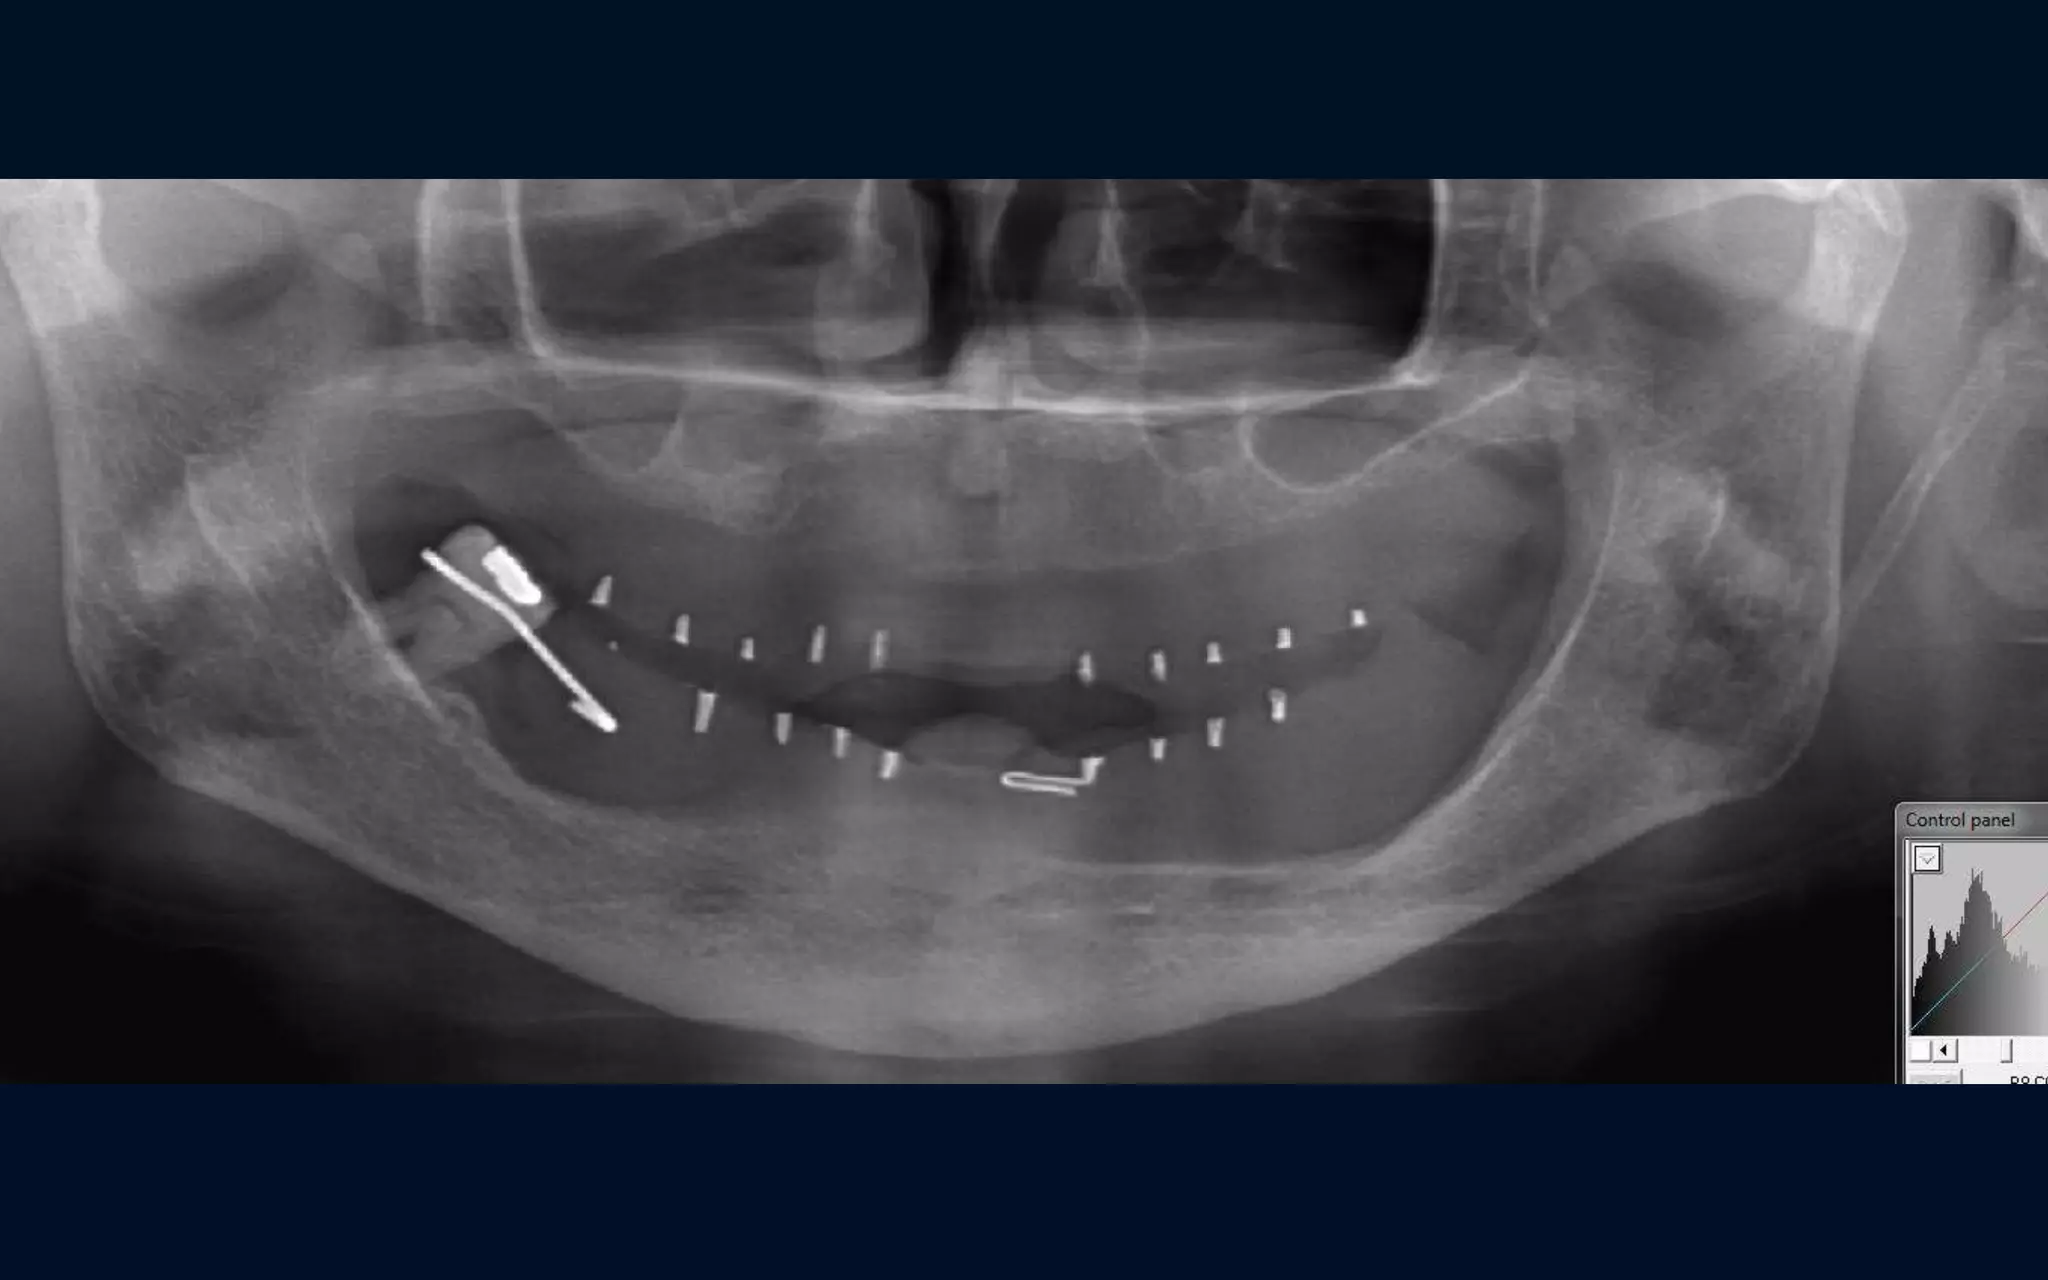

OPG